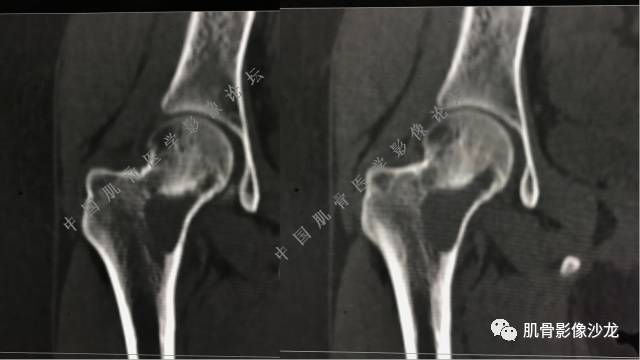

主诉:右髋及右膝部疼痛3月余

现病史:3月前打球时自觉右大腿肌肉拉伤后右髋及右膝部疼痛,自服“活血化瘀”类药物(具体不详)后自觉疼痛缓解,2月前打球时再次扭伤,右髋及右膝部疼痛明显,行走时疼痛加重,自服药物治疗,效果不佳,遂来诊。

医影在线 20:13 干骺端溶骨性破坏,边缘模糊,低密度肿块,似有钙化

Echo 20:13 有骨质破坏,边界不清,有软组织肿块,我觉得恶性是要考虑的

Echo 20:23 我个人觉得,17岁男性,病灶发生在原干骺端区域,溶骨性骨质破坏,似有肿瘤骨,有软组织肿块形成,从常见病发生率来说,骨肉瘤还是要考虑的